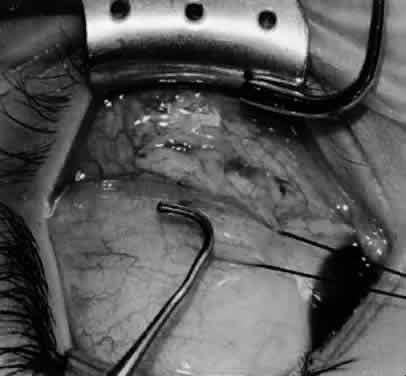

Fig. 14. The inferior temporal vortex vein, 8 mm posterior to the temporal insertion of the inferior rectus muscle, is held on a Green muscle hook.

Fig. 15. The placement of sutures within the sclera for a recession procedure of 10 mm. The anterior suture is placed 3 mm temporal and 2 mm posterior to the lateral insertion of the inferior rectus muscle, and the posterior suture is placed 3 mm further posteriorly.

Fig. 16. Two sutures straddle the inferior temporal vortex vein insertion for a 14-mm recession procedure.

Fig. 17. Knots are tied to show the placement. The inferior oblique muscle is held on a Stevens muscle hook.